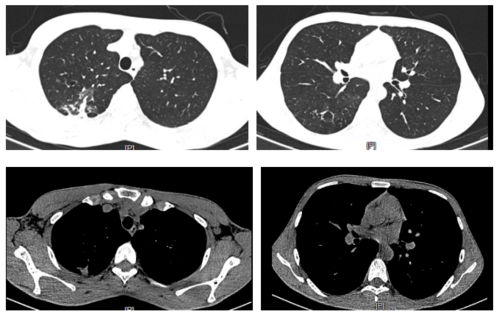

肺结核咳出坏死物图片

肺结核

空洞型肺结核

肺结核ct

肺结核图片

肺结核x光片